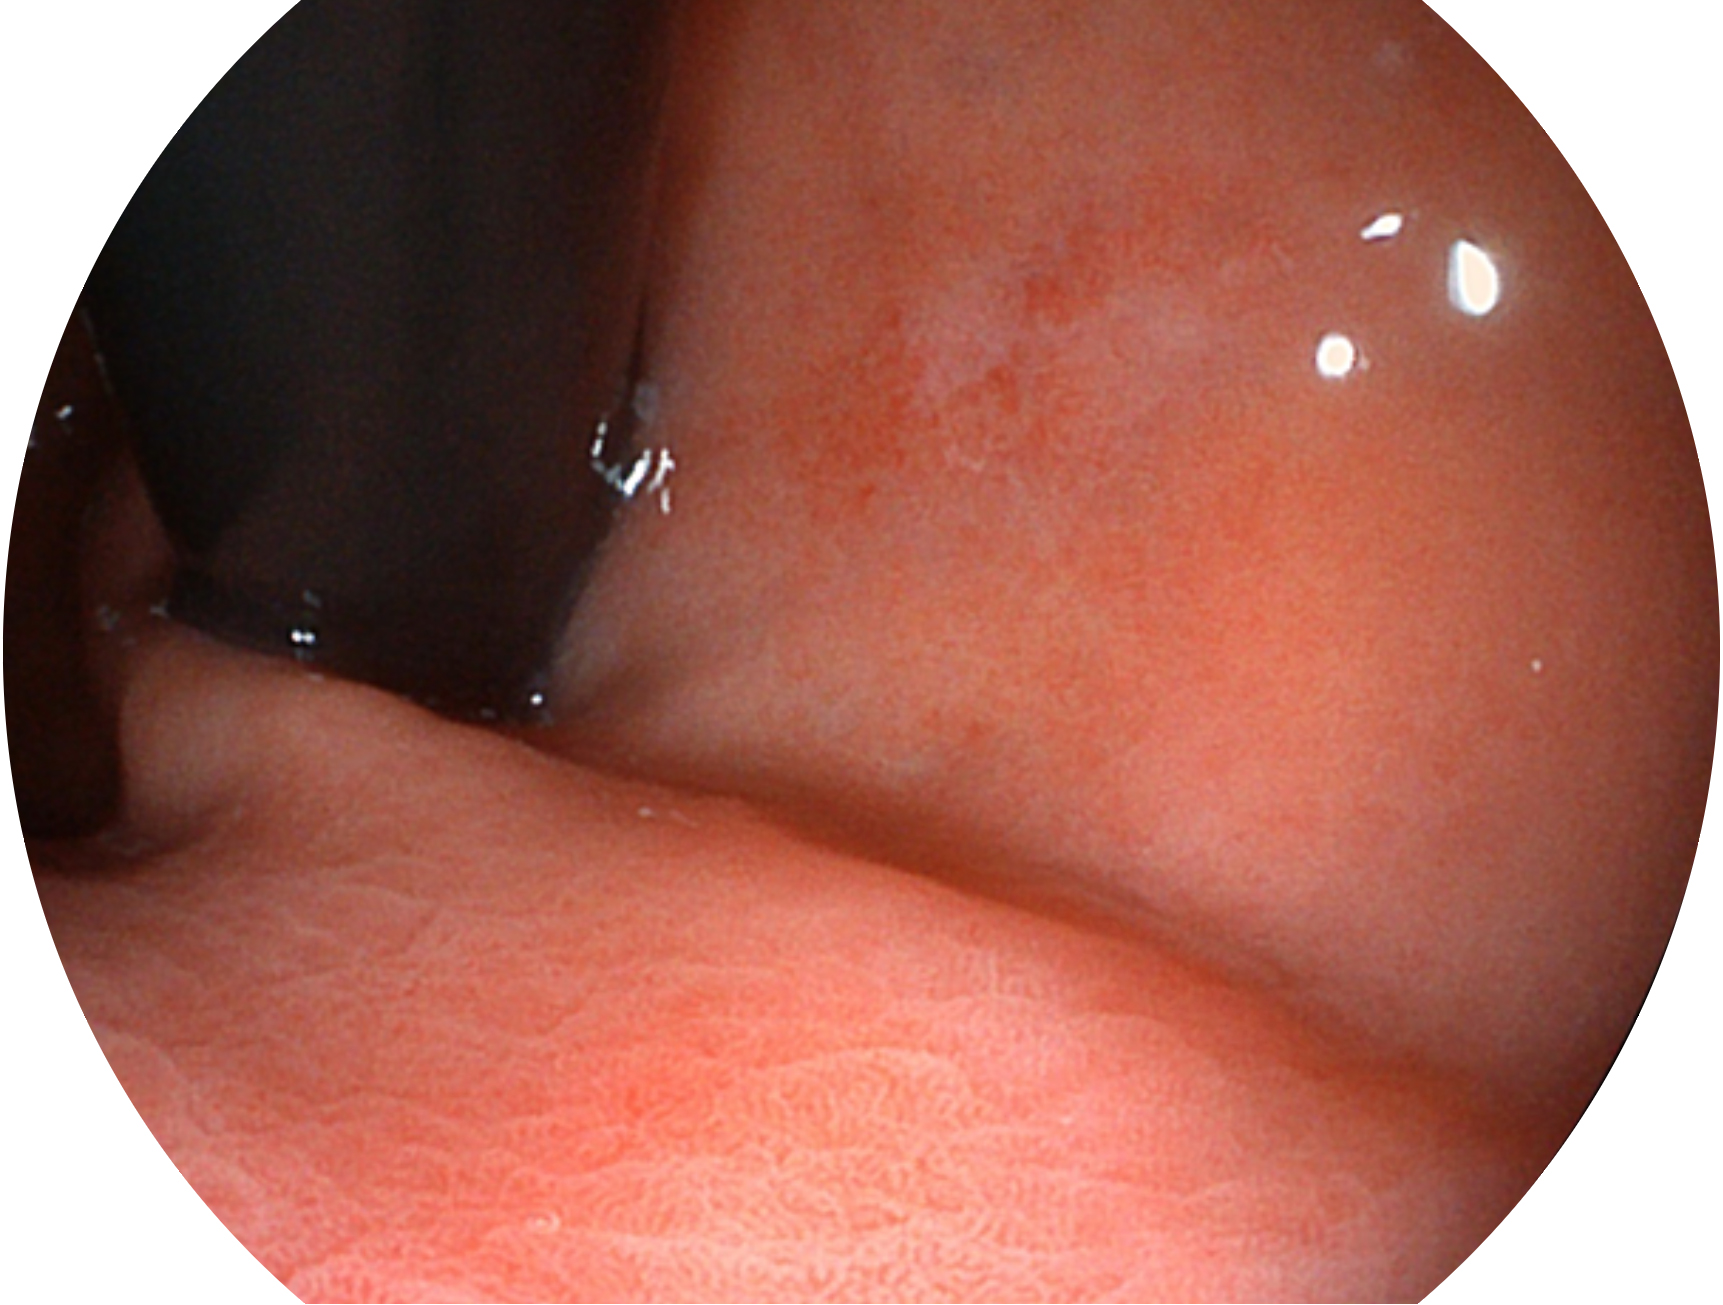

16877太阳集团新开发的内镜染色技术,主要是基于多波长LED 光源的开发,VLS-55Q 四波长LED 光源是由四个不同颜色的LED光按照相应照明模式所规定的特定发光比例进行合束后形成,合束后形成的照明光的光谱由红光、绿光、蓝光及蓝紫光这四个不同的波段范围构成。具有更高光谱自由度,通过光谱比例的控制,实现了聚谱成像技术,英文全称为“Spectral Focused Imaging, SFI”,缩写为“SFI”和光电复合染色成像技术,英文全称为“Versatile Intelligent Staining Technology, VIST”,缩写为“VIST”。